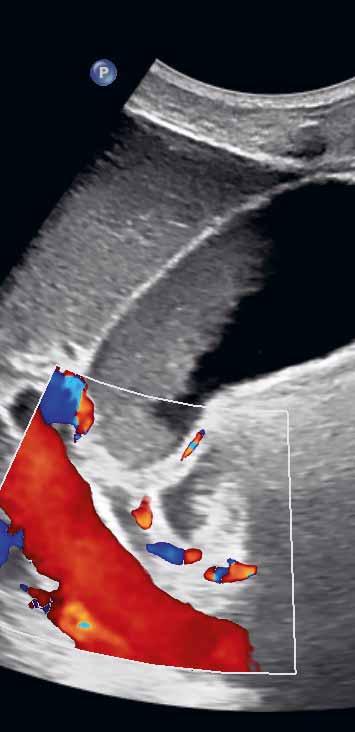

Postprandiálně se mírně dilatuje ductus hepatocholedochus. Potrava přítomná v duodenu ztěžuje zobrazení distálního a intrapankreatického hepatocholedochu. Artefakty z duodena, které naléhá na spodní stěnu žlučníku, mohou imitovat patologii stěny žlučníku či drobnou vícečetnou cholecystolitiázu. Za duodenem však nevzniká typický dorzální akustický stín jako za konkrementy, ale reverberační artefakty v podobě hypoechogenního akustického „šumu“ (obr. 1.2).

Obr. 1.2 Imprese duodena do kaudální stěny žlučníku